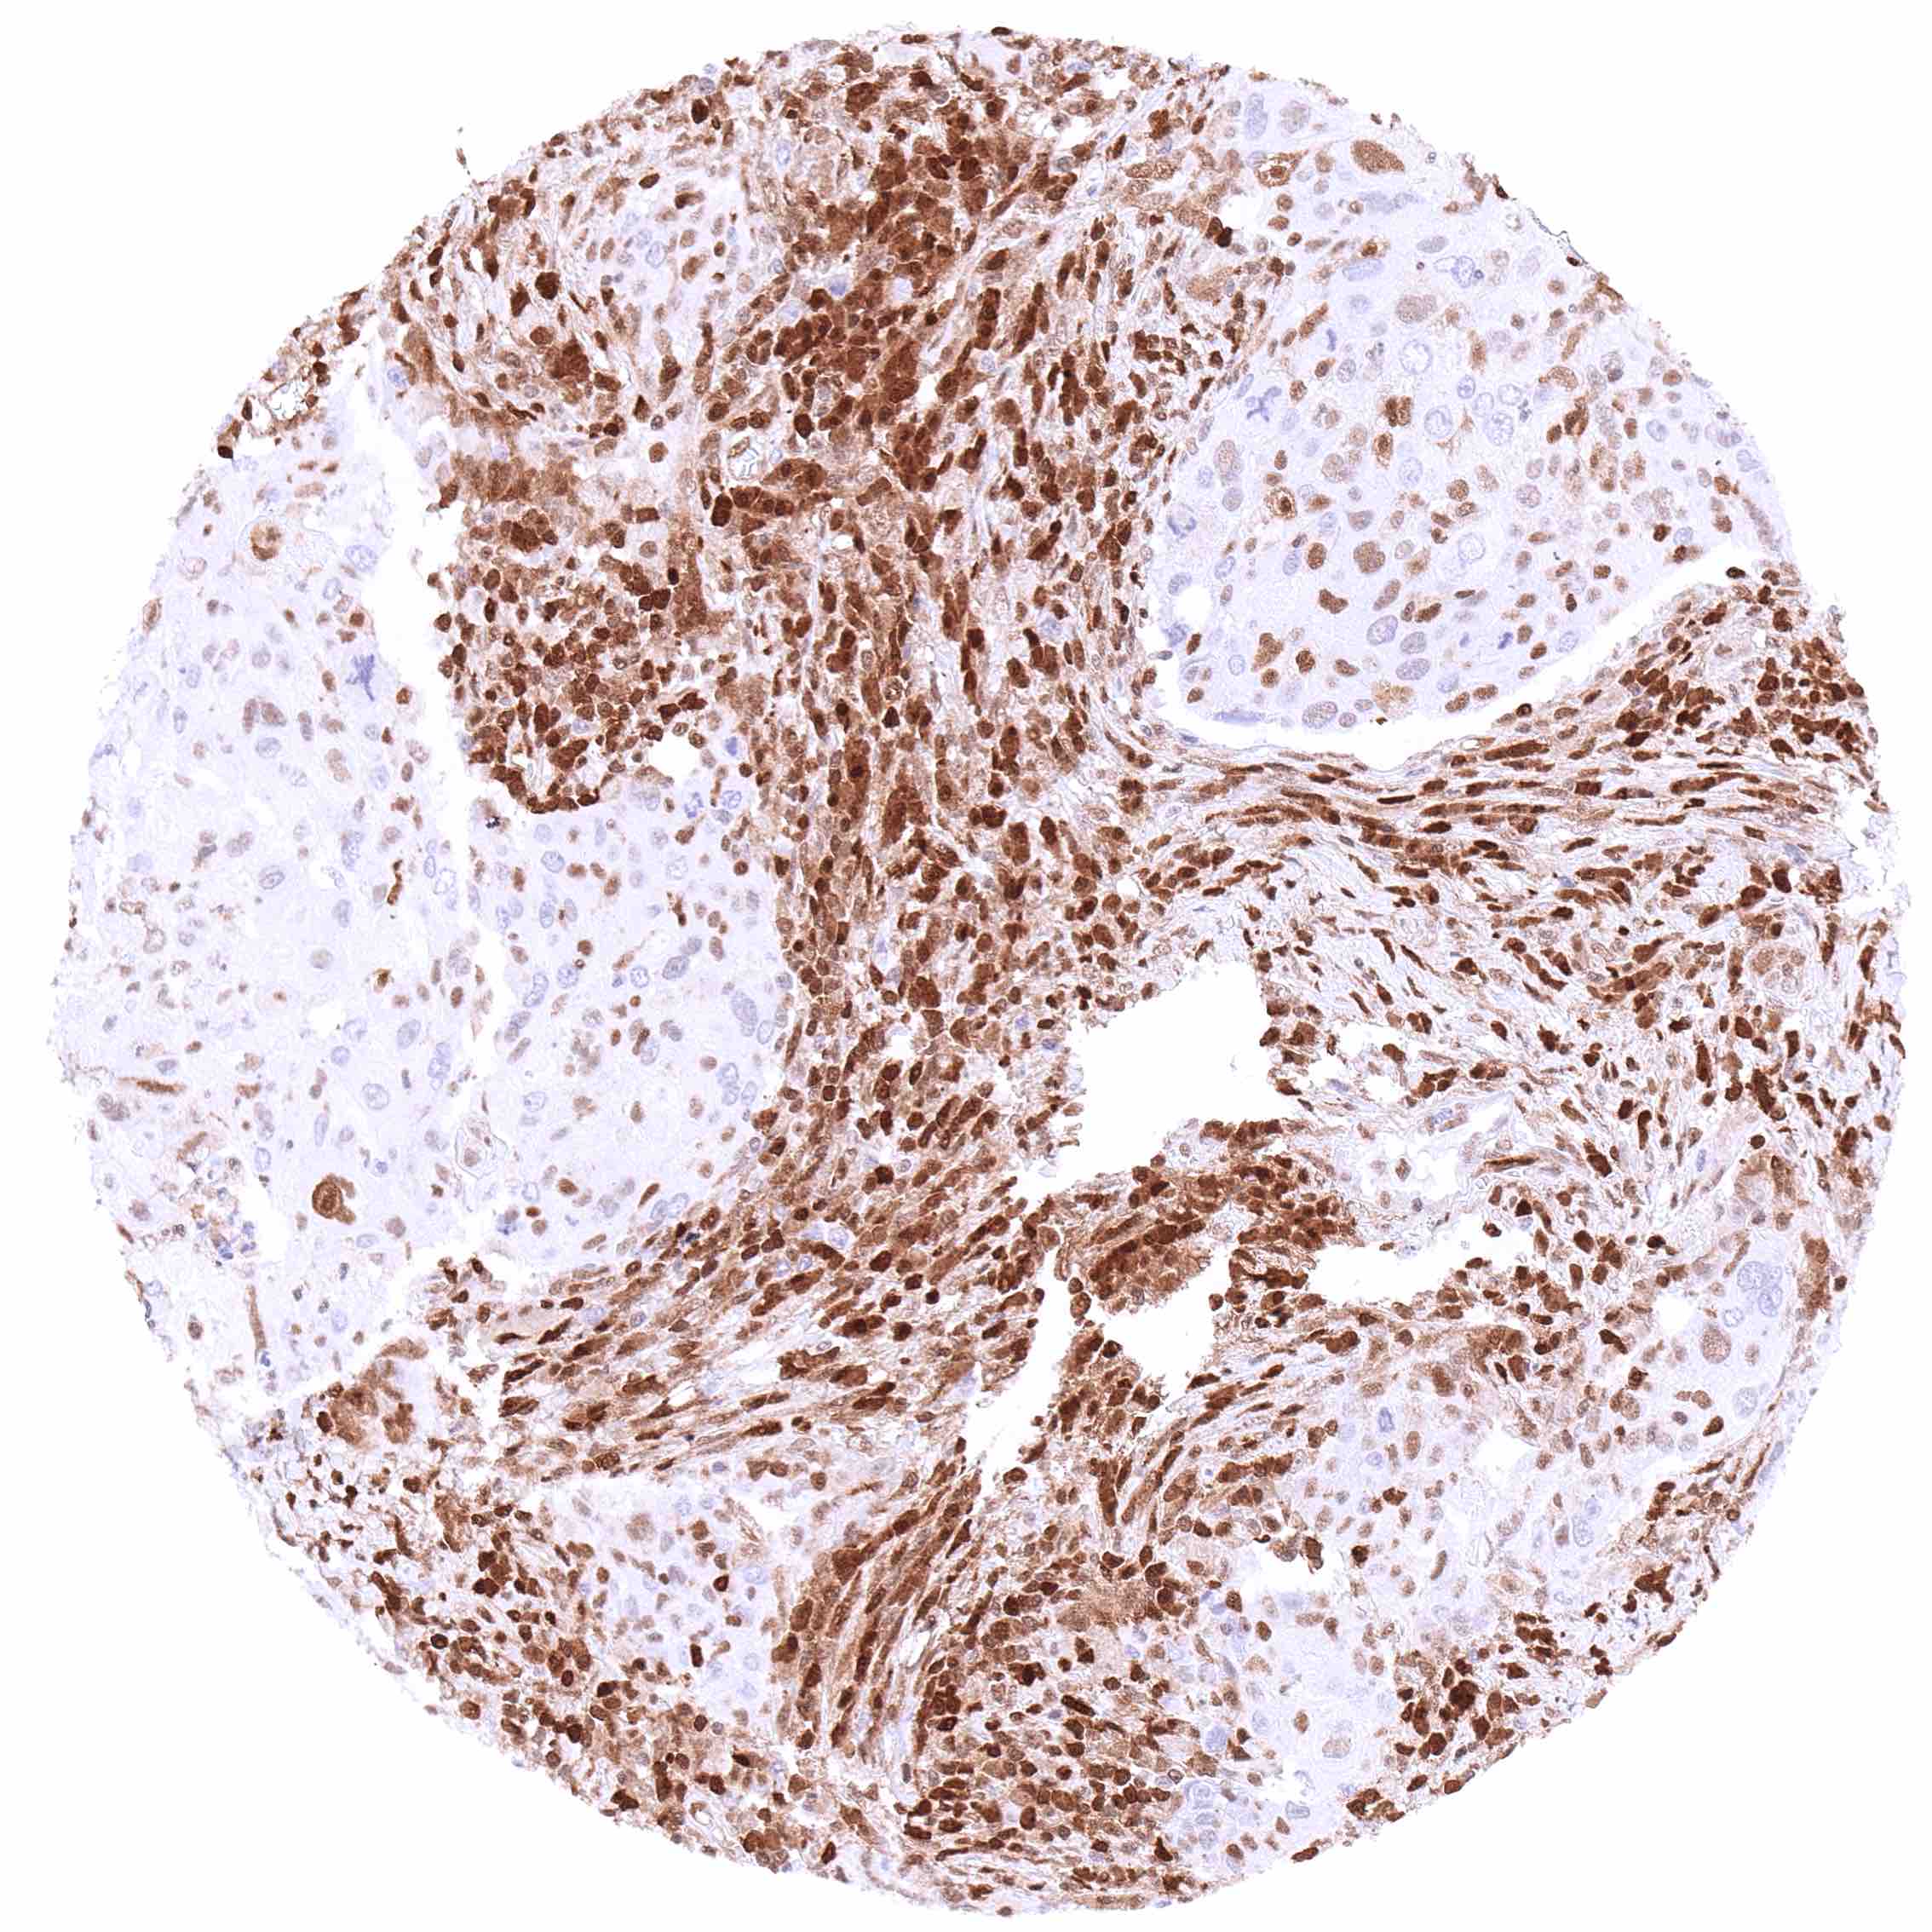

Uterus, cervix – Squamous cell carcinoma with a variable, weak to strong, predominantly cytoplasmic p27 staining of tumor cells.